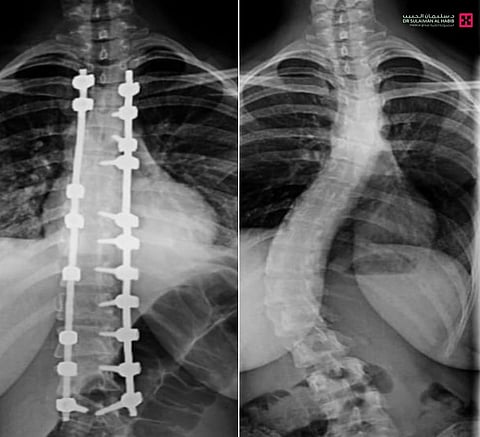

تمكّن فريق طبي في مستشفى الدكتور سليمان الحبيب بالصحافة، من إجراء عملية نوعية ناجحة لتقويم تشوّه متطور بالعمود الفقري لشابة عشرينية، كانت تعاني من ميلان (جنف) بدرجة "55" وتحدّب صدري بمقدار "70" درجة، ما سبّب لها صعوبات في الجلوس والمشي بشكل مستقيم، وأثّر سلبًا على حياتها الاجتماعية والنفسية، ذكر ذلك د. تركي العنزي استشاري المخ والأعصاب وجراحات العمود الفقري المعقّدة، رئيس الفريق الطبي المعالج.

وأوضح د. العنزي أن المراجعة خضعت فور وصولها للمستشفى لفحوصات دقيقة، شملت الأشعة السينية والرنين المغناطيسي، والتي أظهرت وجود ميلان وتحدب متزايد يتطلب تدخلاً جراحيًا عاجلًا.

وأضاف أن العملية استغرقت "5" ساعات، وأُجريت تحت المراقبة العصبية الدقيقة، وشملت تصحيح العمود الفقري على امتداد "12" فقرة عبر تثبيتها ودمجها باستخدام أحدث أنظمة التثبيت الجراحي، مع إغلاق تجميلي للجرح بتقنيات متقدمة تضمن تقليل الآثار مستقبلاً، إضافة إلى إعادة توازن الكتفين وتناسق الخصر، وأسهم في نجاح العملية توفّر أحدث الأجهزة الطبية وكوادر طبية وتمريضية عالية التأهيل.